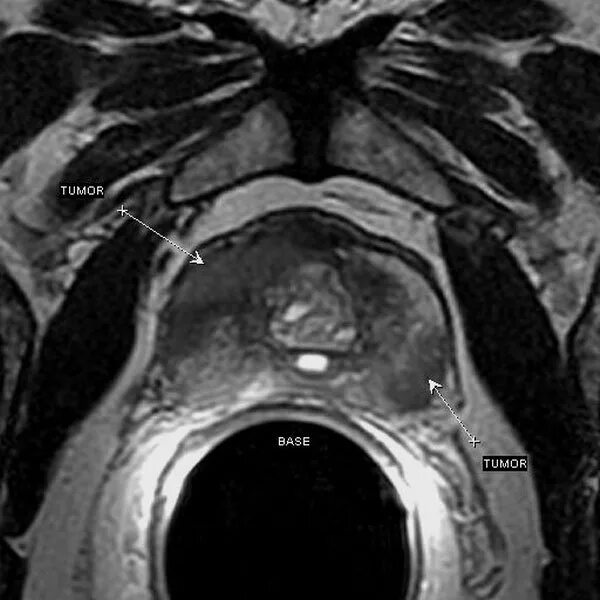

Перед мрт простаты